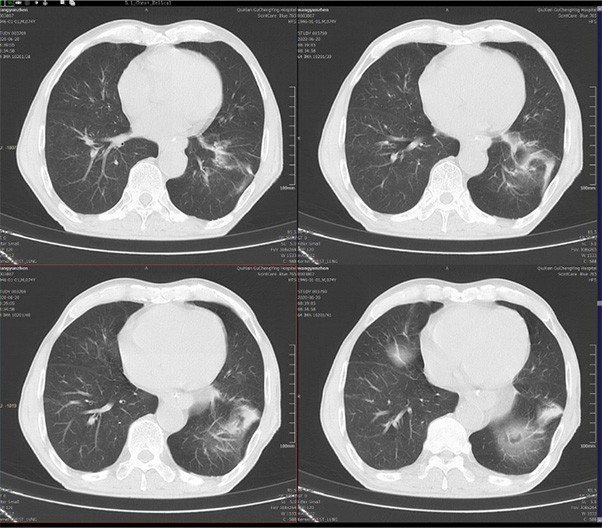

ScintCare Blue 755 | up to 64 slices

ScintCare Blue 755 incorporates an entirely digital integrated ScintiStar detector, which was solely developed by MinFound, from material to the whole structure design, based on the technical know-how of our skilled scientific team. The system produces high-resolution images with a low radiation dose and an excellent signal-to-noise ratio.

NDI NanoDose iteration algorithm is an innovative iterative technique for image reconstruction that takes full advantage of deep learning in anatomical structure in image space as well as model-driven iteration involving tube and detector in projection space, with the aim to generate sharp images in high resolution at the lowest possible dose.

臨床畫廊